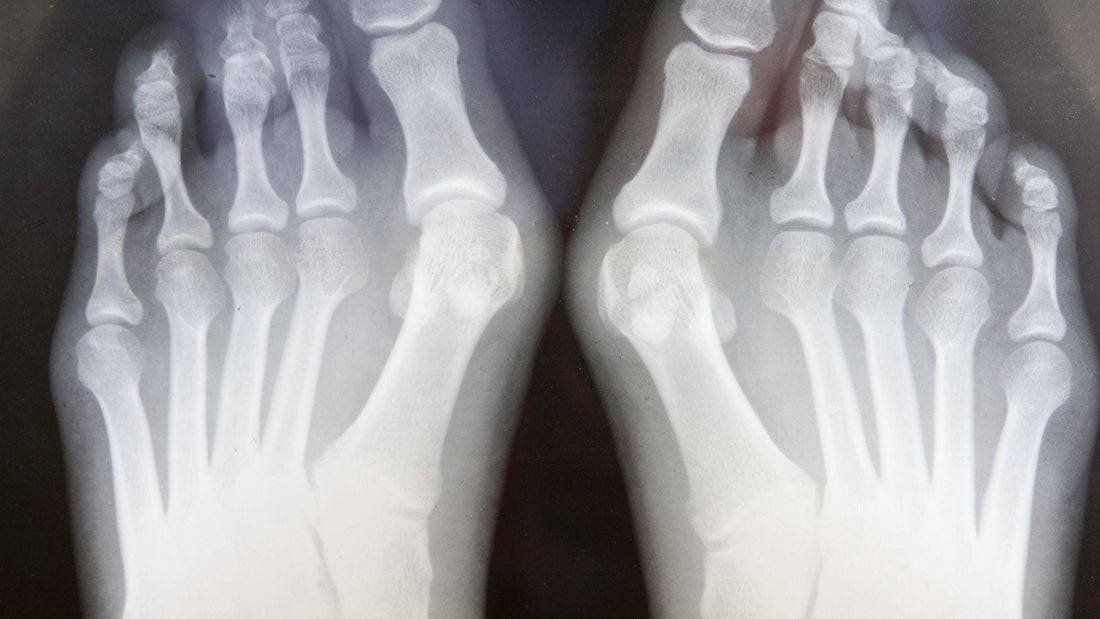

Les oignons ou hallux valgus sont l'une des affections du pied les plus fréquemment diagnostiquées. Curieux de savoir ce qu'est un oignon ? Un oignon est une bosse osseuse qui se forme à l'articulation du gros orteil. Sans soins appropriés des pieds, les oignons peuvent conduire à une intervention chirurgicale comme seul traitement. Il existe également des croyances selon lesquelles les oignons sont génétiques. Notre équipe couvre les causes des oignons, discute de la croyance sur la génétique et de plusieurs solutions de soins des pieds dans un récent blog sur les oignons.

Selon la clinique Mayo, l'hallux valgus ou oignon est une bosse osseuse qui se forme sur l'articulation à la base du gros orteil. Il se produit lorsque certains os de la partie avant du pied se déplacent. De même, la même bosse osseuse peut se former sur l'extérieur du pied, à la base du petit orteil, et on parle alors d'oignons. Dans les deux cas, vous pouvez ressentir des douleurs au pied et avoir besoin d'une intervention chirurgicale si vous ne prenez pas régulièrement soin de vos pieds. Les oignons et les bunionettes font l'objet d'un débat quant à savoir s'il s'agit de problèmes génétiques liés aux pieds ou s'ils sont causés par vos chaussures ou autre chose.